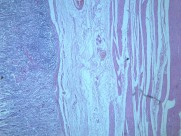

慢性萎缩性胃炎大全(12)张

本病以胃粘膜萎缩变薄,粘膜腺体减少或消失,并伴有肠上皮化生,固有膜内多量淋巴细胞、浆细胞浸润为特点。本性胃炎的病因比较复杂,部分可能与吸烟酗酒和用药不量有关,部分由慢性浅表性胃炎迁移发展而来,还有部分属兔自身免疫疾病。